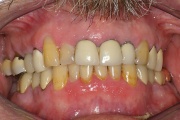

Sjörgeni sündroomist tingitud suukuivus